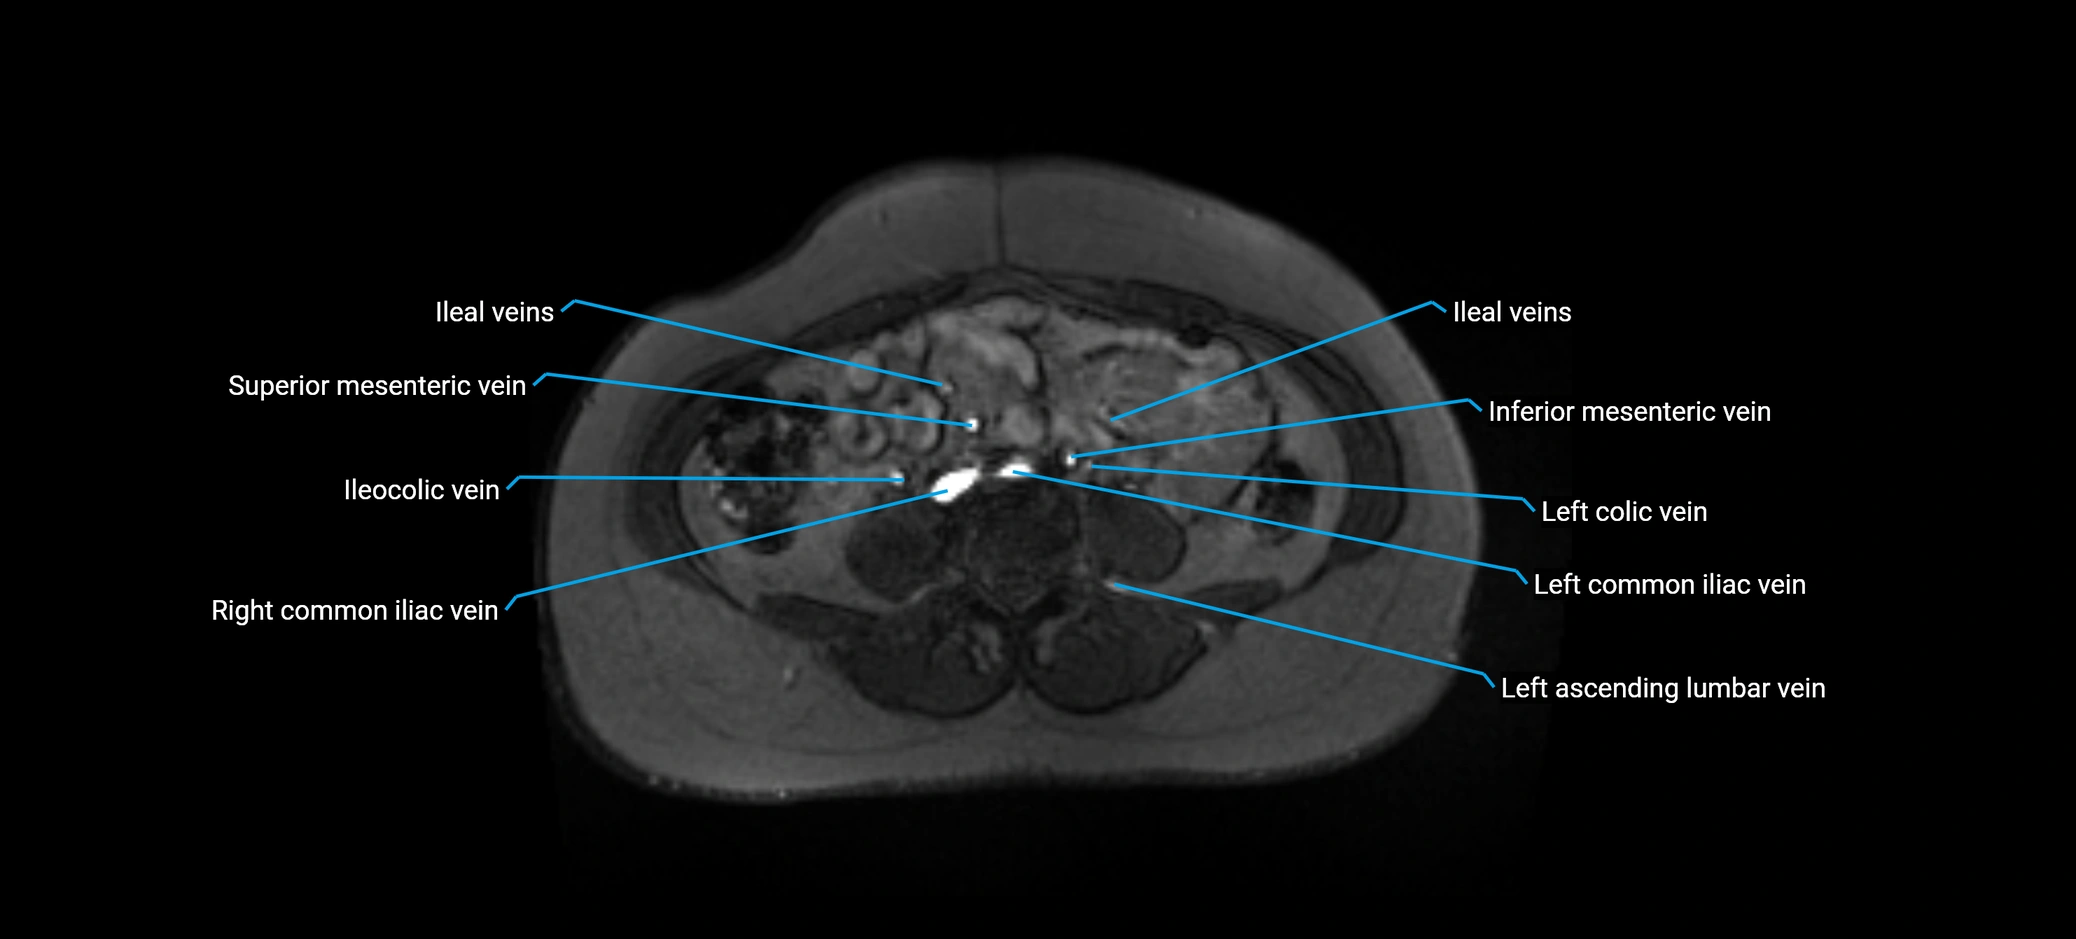

MRI image

image